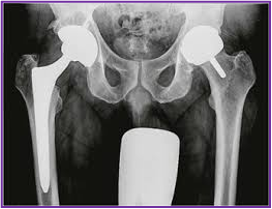

⚪ 3. ábra: Teljes (TEP) és felszínpótló (HR) RTG képe